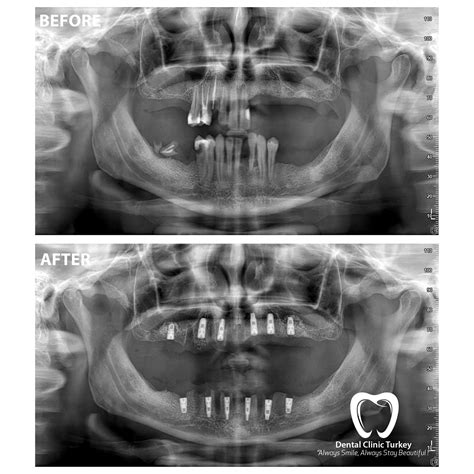

• Treatment Planning: Essential for orthodontic evaluations, implant placement, and detecting cysts or tumors within the jaw.

The transition from traditional film-based X-rays to digital panoramic systems has significantly improved the quality of care. Digital sensors provide a sharper, clearer image that can be enhanced, zoomed, and filtered by your dentist to detect subtle anomalies that might not be visible to the naked eye on physical film. Additionally, digital images are easily stored in your electronic dental record, allowing your care team to track changes in your dental structure over the course of several years.

Being able to view these images on a large screen during your consultation also fosters better communication between you and your dentist. When you can see the structures of your own jaw clearly, it is easier to understand why a specific treatment—such as an implant or an extraction—is being recommended, empowering you to make informed decisions about your own health journey.